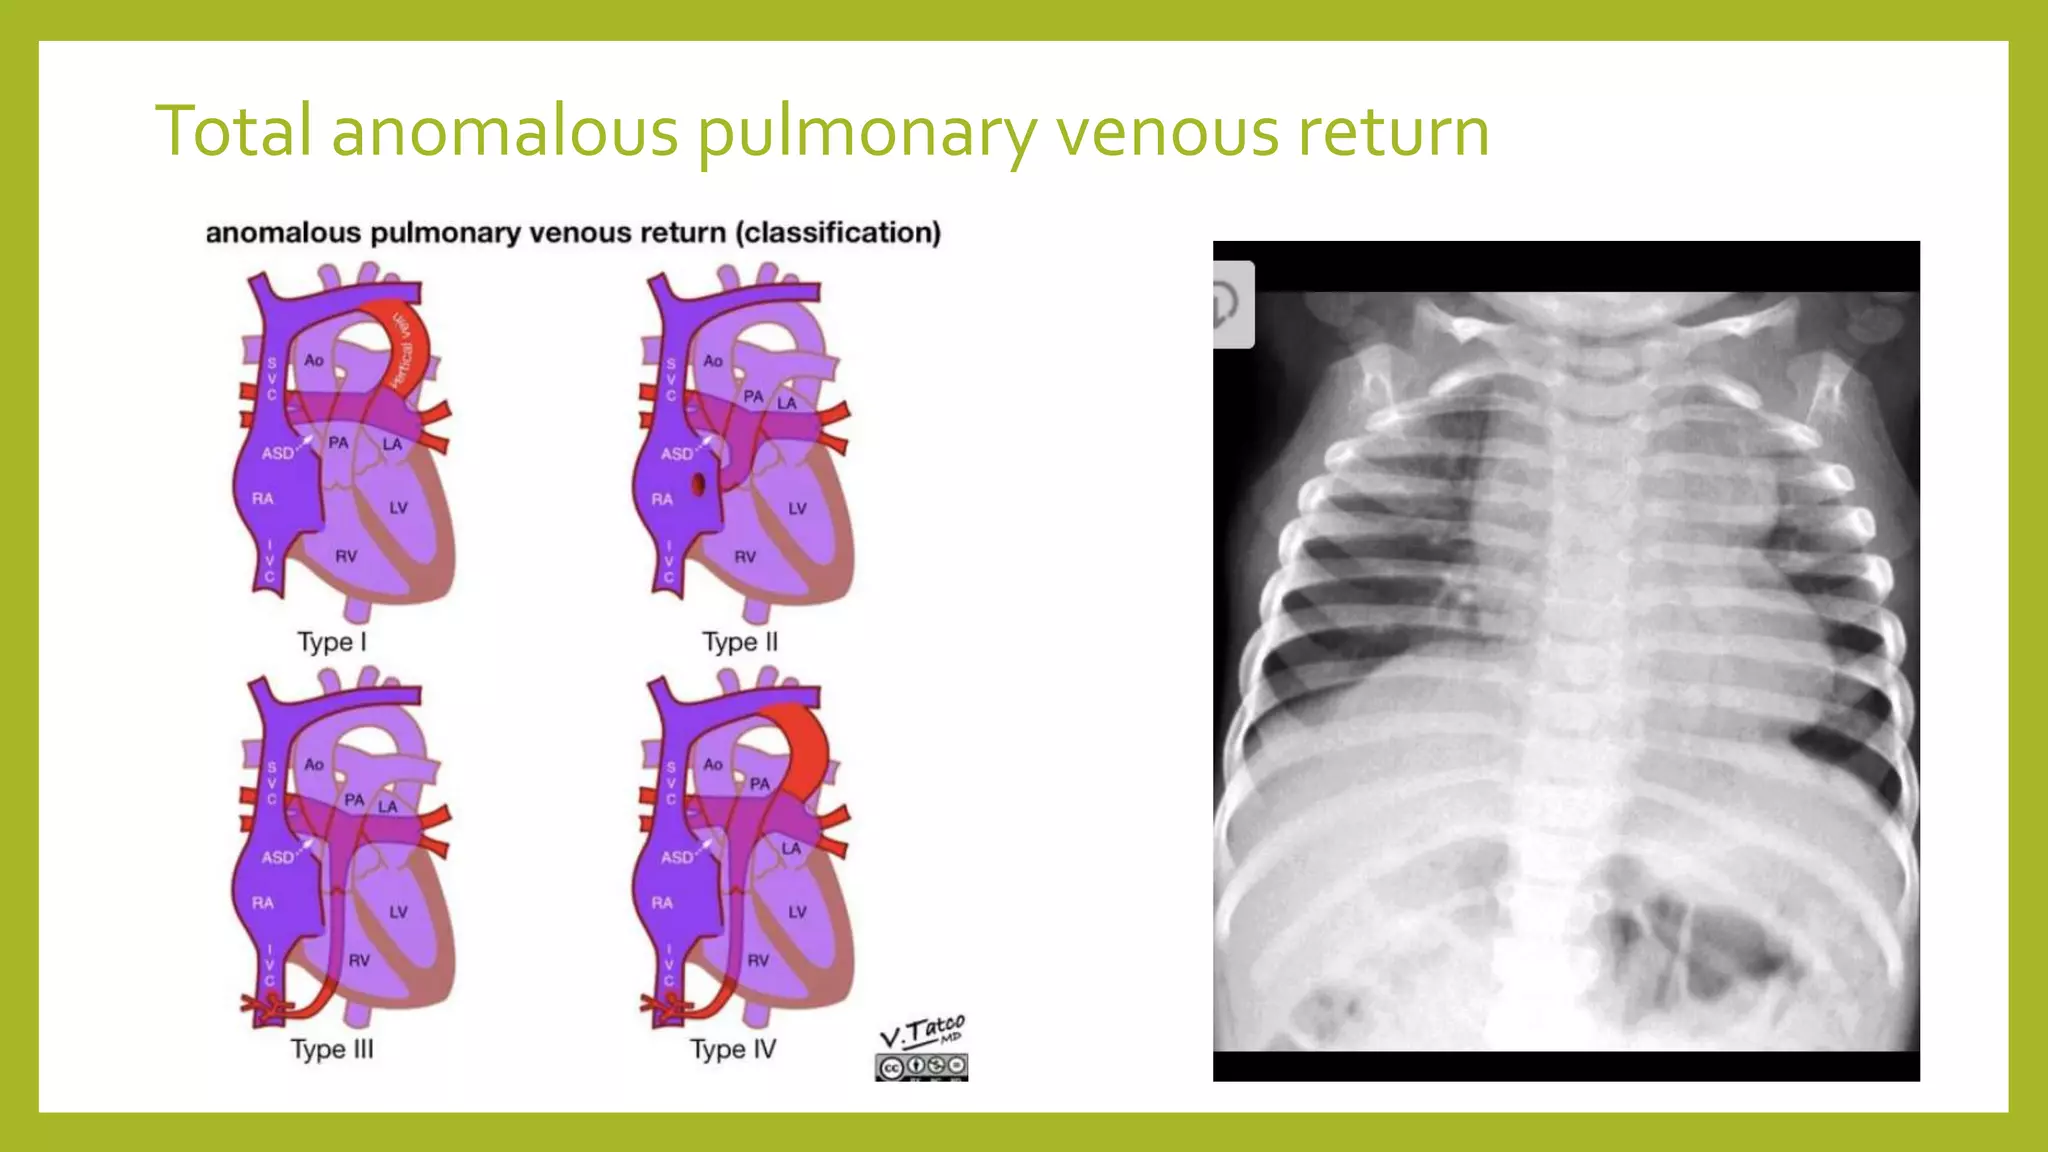

The document provides guidance on approaching and interpreting chest x-rays (CXR). It outlines steps to check the name, date and quality of the film, systematically scan the CXR looking for abnormalities, and determine if the lungs appear too white or black. Specific signs are described to help localize abnormalities, including the cardiac silhouette sign and pleural effusion signs. Examples are given of respiratory distress syndrome, tetralogy of fallot, transposition of great arteries, and total anomalous pulmonary venous return. The take home message is to summarize positive findings, compare to prior CXRs if available, and confirm findings with a radiologist.